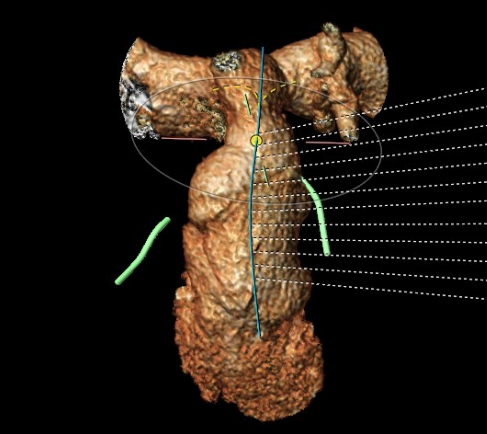

患者女性,15岁,15年前行“法洛四联症矫治术”,此次因“活动后心累、气促3年余”入院,心脏彩超提示:肺动脉前向血流通畅,肺动脉瓣重度反流。术前CT评估提示主肺动脉主干呈倒漏斗型(近端明显粗于远端),且主肺动脉总长仅3cm,左右肺动脉近分叉处均存在狭窄,尤其是左肺动脉开口处狭窄明显。

在安琪教授的主持下,多学科讨论后认为该患者上述解剖特点不适合目前经股静脉入路植入的介入肺动脉瓣,可考虑使用佰仁医疗Salus介入肺动脉瓣经心尖入路实施肺动脉瓣植入。在心脏大血管外科安琪教授主持下,心脏内科冯沅教授带领赵振刚副教授及李翔医师与心脏大血管外科罗书画副主任医师及李东旭主治医师合作完成了手术。术中手术团队经股静脉完成心导管检查及造影后,通过肋间小切口暴露右室心尖并预置荷包缝线,穿刺右室心尖建立经心尖入路,而后分别经股静脉和心尖进行左、右肺动脉球囊对吻扩张,最后经心尖完成肺动脉瓣植入。术后TEE提示肺动脉瓣植入位置理想、固定良好,无瓣周漏或中央反流,左、右肺动脉显影正常。肋间切口长度仅2.5cm,总体手术效果满意。

CT重建肺动脉